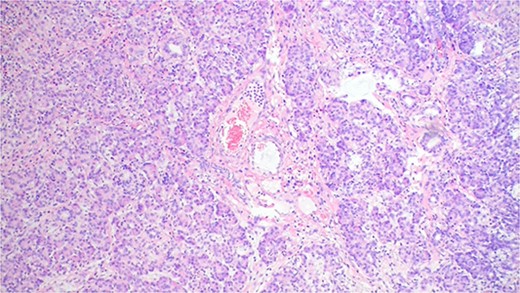

The patient commenced oral intake three days following the operation and was discharged seven days later. The postoperative pathology report indicated chronic diverticulitis with ectopic pancreatic mucosa and chronic appendicitis (Figs 3 and 4).

The pathology result of chronic diverticulitis with ectopic pancreatic mucosa.